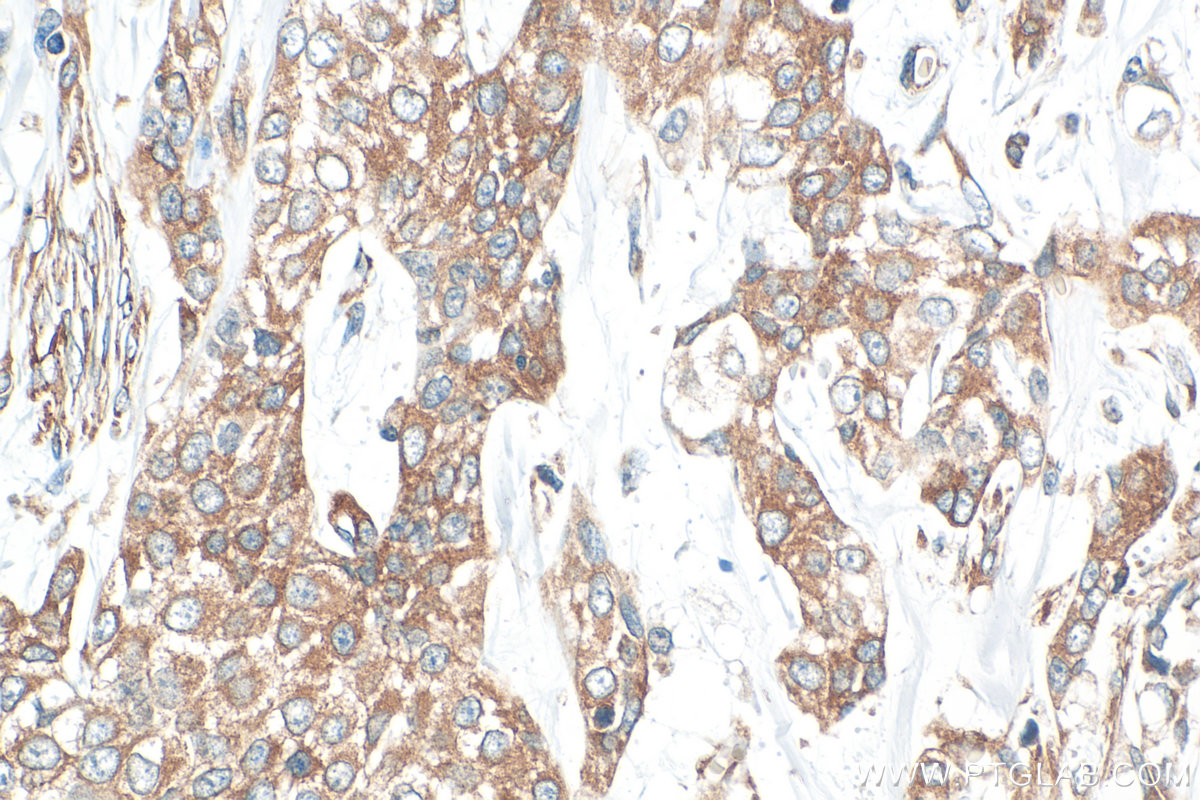

| Positive IHC detected in | human intrahepatic cholangiocarcinoma tissue, human urothelial carcinoma tissue Note: suggested antigen retrieval with TE buffer pH 9.0; (*) Alternatively, antigen retrieval may be performed with citrate buffer pH 6.0 |

| Immunohistochemistry (IHC) | IHC : 1:200-1:800 |